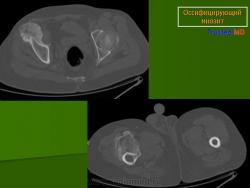

Рентгенологические признаки однотипны для всех форм оссифицирующего миозита; плотный рисунок периферической и менее плотный центральной части повреждения.

При компьютерной томографии визуализируется кальцификация гетеротопической кости, которая продвигается от наружного края образующегося узла в центр.

Рентгенологические признаки однотипны для всех форм оссифицирующего миозита; плотный рисунок периферической и менее плотный центральной части повреждения.